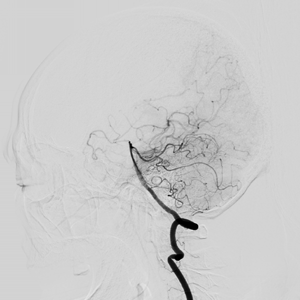

流行病学研究基本上将脑卒中分为出血性卒中和缺血性卒中两大类。出血性脑血管病包括:颅内动脉瘤、脑血管畸形、高血压脑出血等。

缺血性脑血管病包括各种病因如颅内动脉狭窄、颈动脉狭窄、椎动脉狭窄、锁骨下动脉狭窄、烟雾病(Moyamoya病)、动脉粥样硬化疾病或心源性疾病导致的脑缺血。在我国急性缺血性脑卒中是最常见的卒中类型,约占脑卒中的69.6%~70.8%,在空间分布上有北方高、南方低的趋势,这与高血压患病率的空间分布几乎一致。急性缺血性脑卒中的处理包括早期诊治、早期预防再发(二级预防)和早期康复。随着医疗技术水平的提升及医学材料科学的进步,缺血性卒中的治疗由早期的静脉药物溶栓治疗发展为血管内溶栓、急诊支架取栓等多种治疗方式。而对于预防缺血性脑卒中事件的发生,颈动脉内膜剥脱术、脑血管搭桥手术、责任血管的球囊扩张加支架置入术等多种治疗方案亦发挥着不可替代的作用。

脑卒中的诊疗是一项系统工程,需要公立三甲医院多部门、多科室的配合协调,建立一个快捷的绿色通道,最终实现对脑卒中的有效救治。北京积水潭医院神经外科通过前期人才储备、交流学习,目前已建立了脑血管病的介入诊疗及多种外科手术治疗的整体治疗方案,同步开通了脑血管病筛查门诊和缺血性脑血管病专病门诊,并已开展了相应的手术,更好地服务于患者。